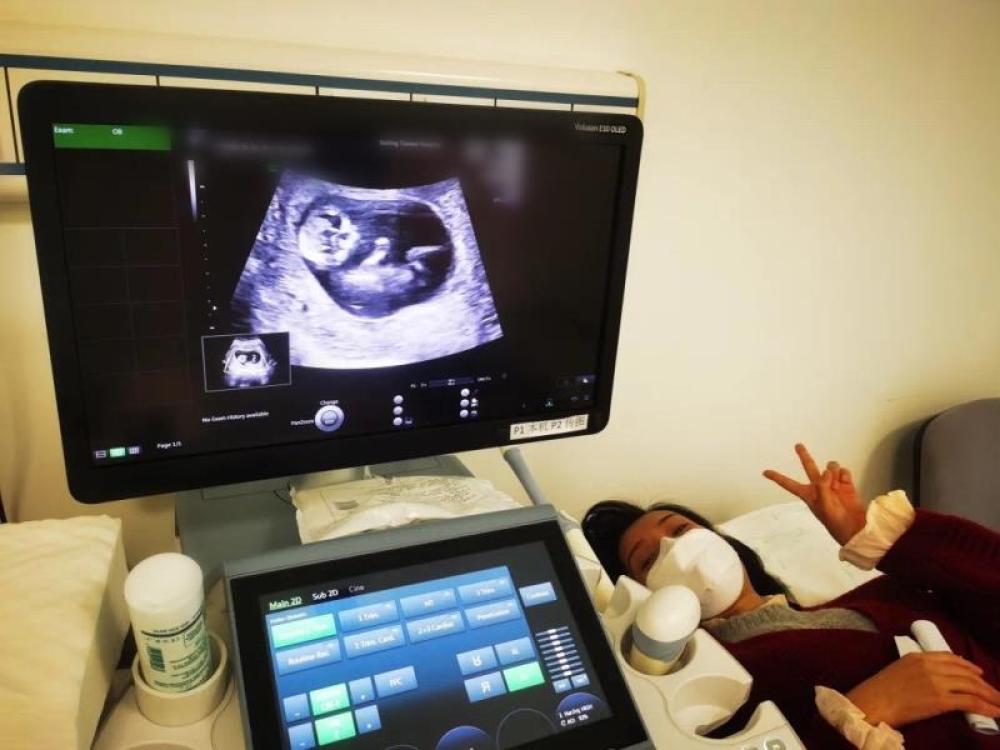

今天是我來武漢的第54天,第一次通過B超影像見到了“小家伙”。

今天一早,妻子去醫院進行B超檢查,同事用手機拍攝下了B超顯示屏上的畫面,記錄下了這個87天的小家伙第一次“亮相”。

圖為北京天壇醫院袁磊愛人做B超檢查。

“袁磊,看看你們家寶寶,可愛嗎?”收到同事發來的視頻,第一眼就看哭了,身邊的同事看完視頻也哭了。

視頻里,這個小家伙好像聽到了外面的召喚,在媽媽的肚子里伸手、踢腿、翻身,用各種動作進行回應……看到他那小胳膊小腿,一種從未有過的幸福感不停地向上涌,眼淚怎么也控制不住。

其實在武漢這么多天,他一直就是我的牽掛,今天終于看到他了,那種感受真是又緊張又激動,雖然還看不清他的樣子,但是已經感受到他的活力。